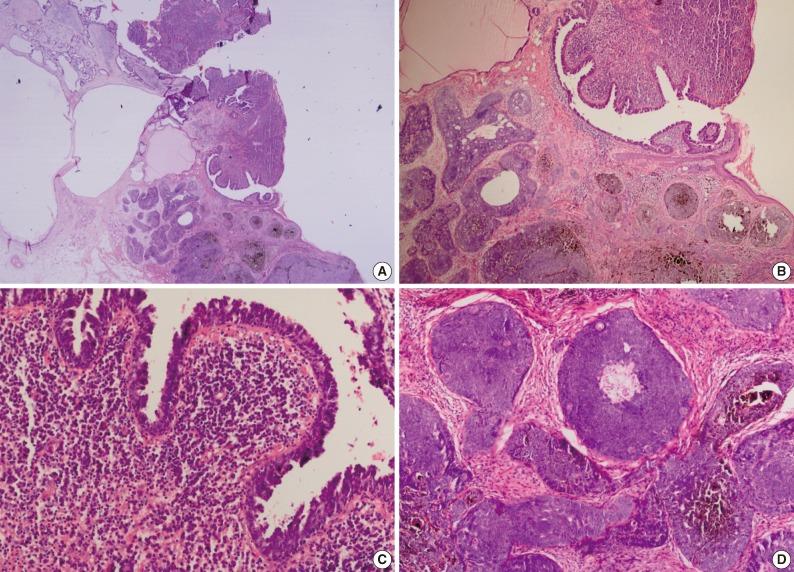

Nevus sebaceus of Jadassohn is a congenital cutaneous hamartoma comprised of multiple skin structures. It has the potential to develop into variety of neoplasms of various epidermal adnexal origins. While multiple tumors may occasionally arise, it is unusual for more than four tumors to arise simultaneously within a single sebaceus nevus. Here in, we report a case of a 70-year-old woman with six neoplastic proliferations including a syringocystadenoma papilliferum, pigmented trichoblastoma, tubular apocrine adenoma, sebaceoma, tumors of follicular infundibulum and superficial epithelioma with sebaceus differentiation arising in a long standing nevus sebaceus on the scalp. Our case is extraordinary because a single nevus sebaceus contained six neoplastic proliferations with differentiation toward the folliculosebaceous-apocrine unit.

Jadassohn皮脂腺痣是一种由多种皮肤结构组成的先天性皮肤错构瘤。它有可能发展成各种起源于表皮附属器的肿瘤。虽然偶尔可能会出现多个肿瘤,但在单个皮脂腺痣内同时出现四个以上肿瘤的情况并不常见。在此,我们报告一例70岁女性病例,其头皮上长期存在的皮脂腺痣发生了六种肿瘤性增殖,包括乳头状汗管囊腺瘤、色素性毛母细胞瘤、管状大汗腺腺瘤、皮脂腺瘤、毛囊漏斗部肿瘤以及具有皮脂腺分化的浅表上皮瘤。我们的病例非同寻常,因为单个皮脂腺痣包含六种向毛囊皮脂腺大汗腺单位分化的肿瘤性增殖。